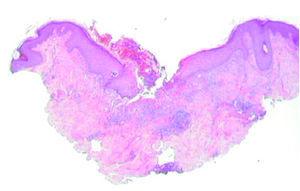

Se realizó cultivo de las lesiones, que se procesó para aerobios, anaerobios, micobacterias y hongos con resultado negativo. Se realizó, además, una biopsia cutánea; en el estudio histológico se apreciaba un epitelio con acantosis e hiperqueratosis, con una invaginación central ocupada por queratina ortoqueratósica y paraqueratósica, celularidad inflamatoria, material necrótico y elementos de tejido conjuntivo (fig. 2). En esta zona y a mayor aumento se observaban haces de colágeno dispuestos verticalmente y atravesando la epidermis. La dermis mostraba cambios degenerativos y un infiltrado inflamatorio mixto (fig. 3). No se apreció la localización folicular ni restos de folículo piloso, a pesar de la realización de múltiples cortes histológicos.

Fig. 2.--Se aprecia la rotura de la epidermis (aumentos y fución). (Hematoxilina-eosina, ×2.)